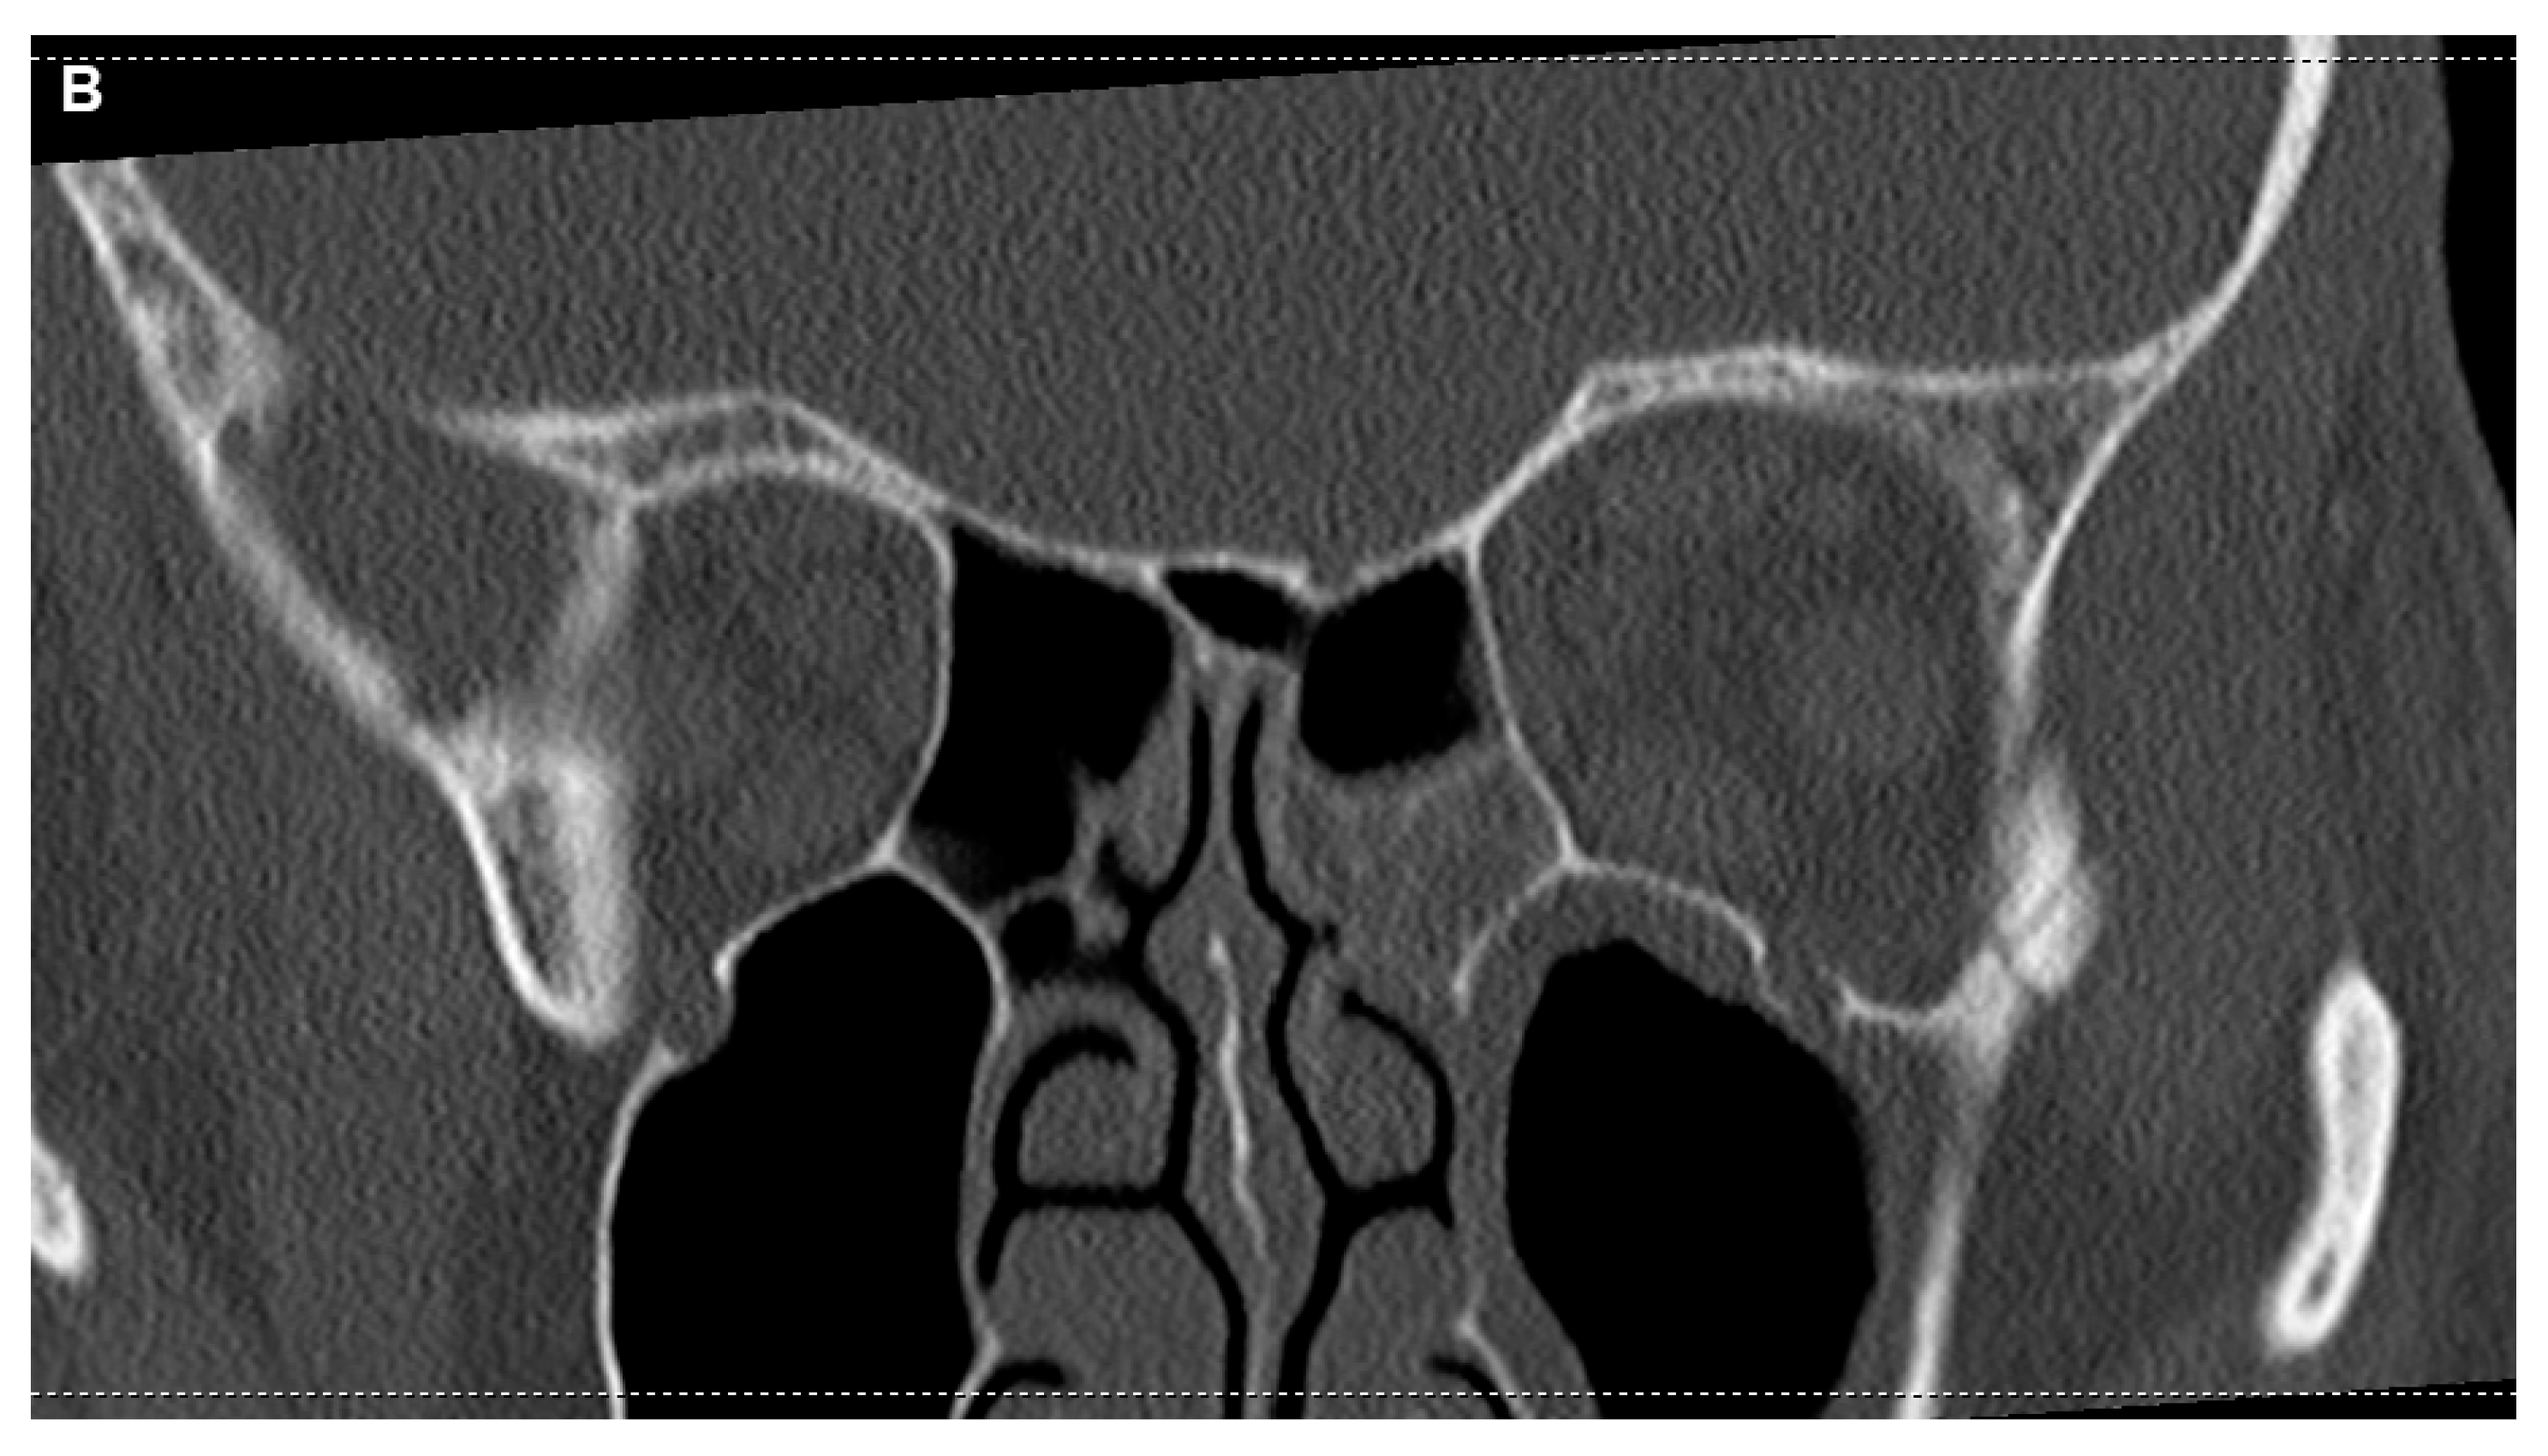

Figure 3.

CT imaging of the orbit and paranasal sinuses. The axial view reveals soft tissue swelling of the left periorbital region, with both globes appearing intact. There was no evidence of intra- or extraconal hematoma or abscess. Notably, increased vascular markings and fat imbibition within the left orbit as well as swelling of the external orbital muscles were visible, suggesting inflammatory changes. Mucosal swelling was present in the paranasal sinuses; however, the bone structures were not affected at all (A). A coronal view shows partial opacificagion of the left sphenoid sinus, which retinas some aeration. Despide this, following further consultation with ENT specialists, it was considered unlikely that the paranasal sinuses were the primary source of the patient’s symptoms. While partial opacification of the left sphenoid sinus was observed, it remained partially aerated.